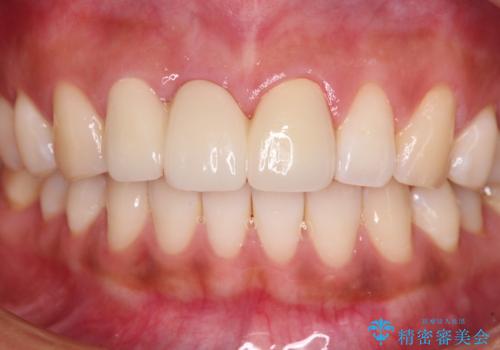

折れているのに応急処置でごまかしてきた前歯 オールセラミックブリッジによる補綴治療

抜歯による歯槽骨や歯肉が陥没して審美障害を起こすことがありますが、今回は仮歯でも違和感のない外観となったため、歯肉移植術を行うことなく仕上げることができました。